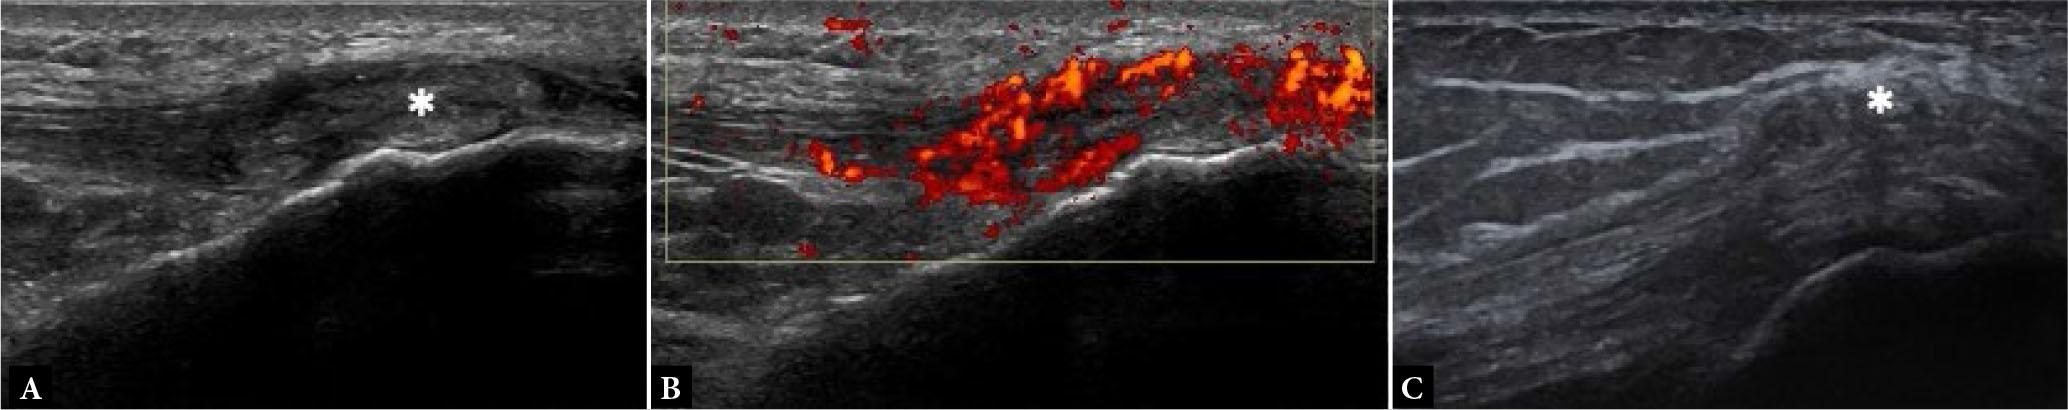

On HRUS, enthesitis appears as heterogeneous hypoechogenicity of the enthesis, loss of normal fibrillar echotexture of the tendon insertion, intratendinous hypoechoic areas, punctate calcific foci, blurring of tendon margins, thickening of the insertion site of tendon, irregularities, and erosions of subentheseal bone, and perientheseal swelling (Fig. 15). Perientheseal diffusion of inflammatory fluid noted on imaging has been reported to be a characteristic finding of SpA and cause perientheseal swelling(22). Multiple and irregular enthesophytes and calcific deposits are more specific for SpA-related enthesitis(22). PDUS can show an increased signal in active inflammation of the enthesis and can be used to assess treatment response (Fig. 16).

Enthesitis. Long-axis US images of Achilles tendon show loss of normal fibrillar echotexture and decreased echogenicity of the tendon insertion (asterisks), punctate calcific foci (small arrow in B), erosions of subentheseal bone (large arrows in A and B) and power Doppler signal at enthesis as seen in B

Enthesitis. Short-axis grayscale (A) and power Doppler (B) US images of tibialis posterior tendon (asterisks) show intra-tendinous and peritendinous thickening and power Doppler signal